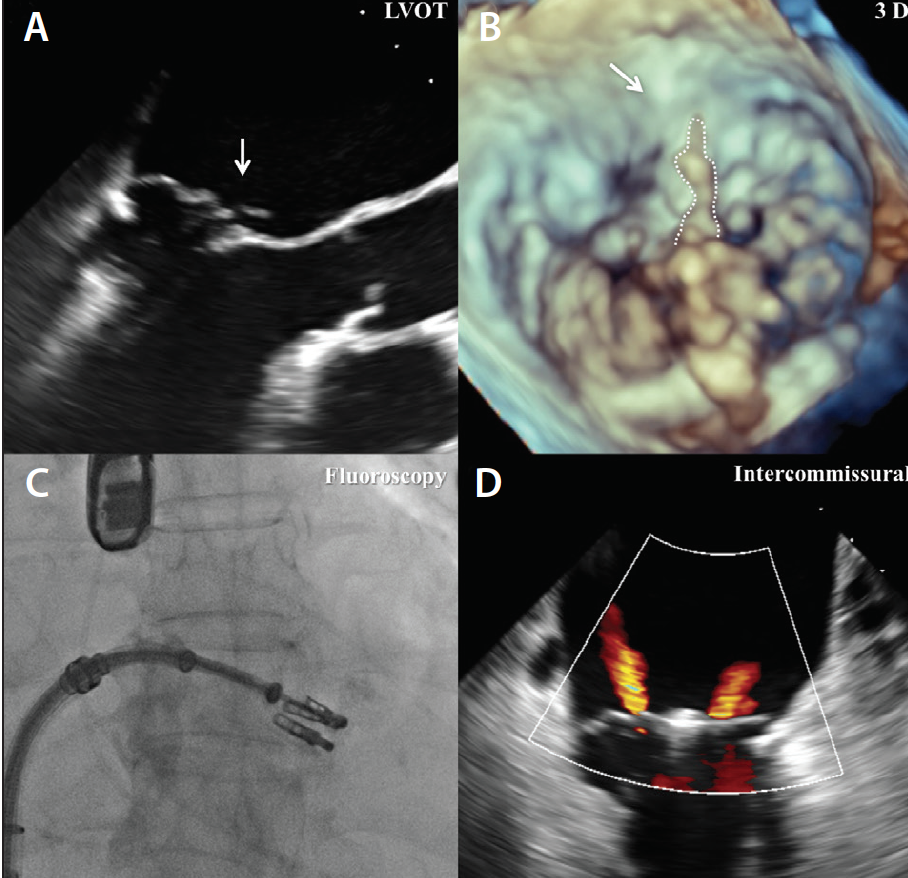

Figure 1. Example of degenerative MR due to flail leaflet; primary pathology was clipped by the first MitraClip; however, there was significant residual jet on the lateral side of the first clip. The second MitraClip was placed lateral to the first MitraClip. Final MR was mild on transesophageal echocardiography. Left ventricular outflow tract (LVOT) view showing P2 mitral valve scallop flail with torn chord (A). Threedimensional view showing P2 mitral valve scallop flail with torn chord (B). Additional clip being placed laterally after first clip placed on primary pathology (C). Intercommissural view showing mild MR with two MitraClips (D).